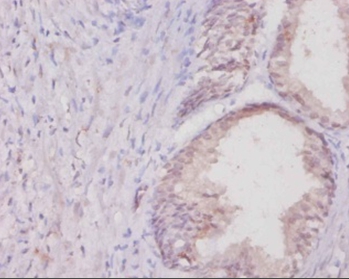

Immunohistochemical analysis of paraffin-embedded human colon cancer using #42130 at dilution of 1:20.

,

Immunohistochemical analysis of paraffin-embedded human colon cancer using #42130 at dilution of 1:50.